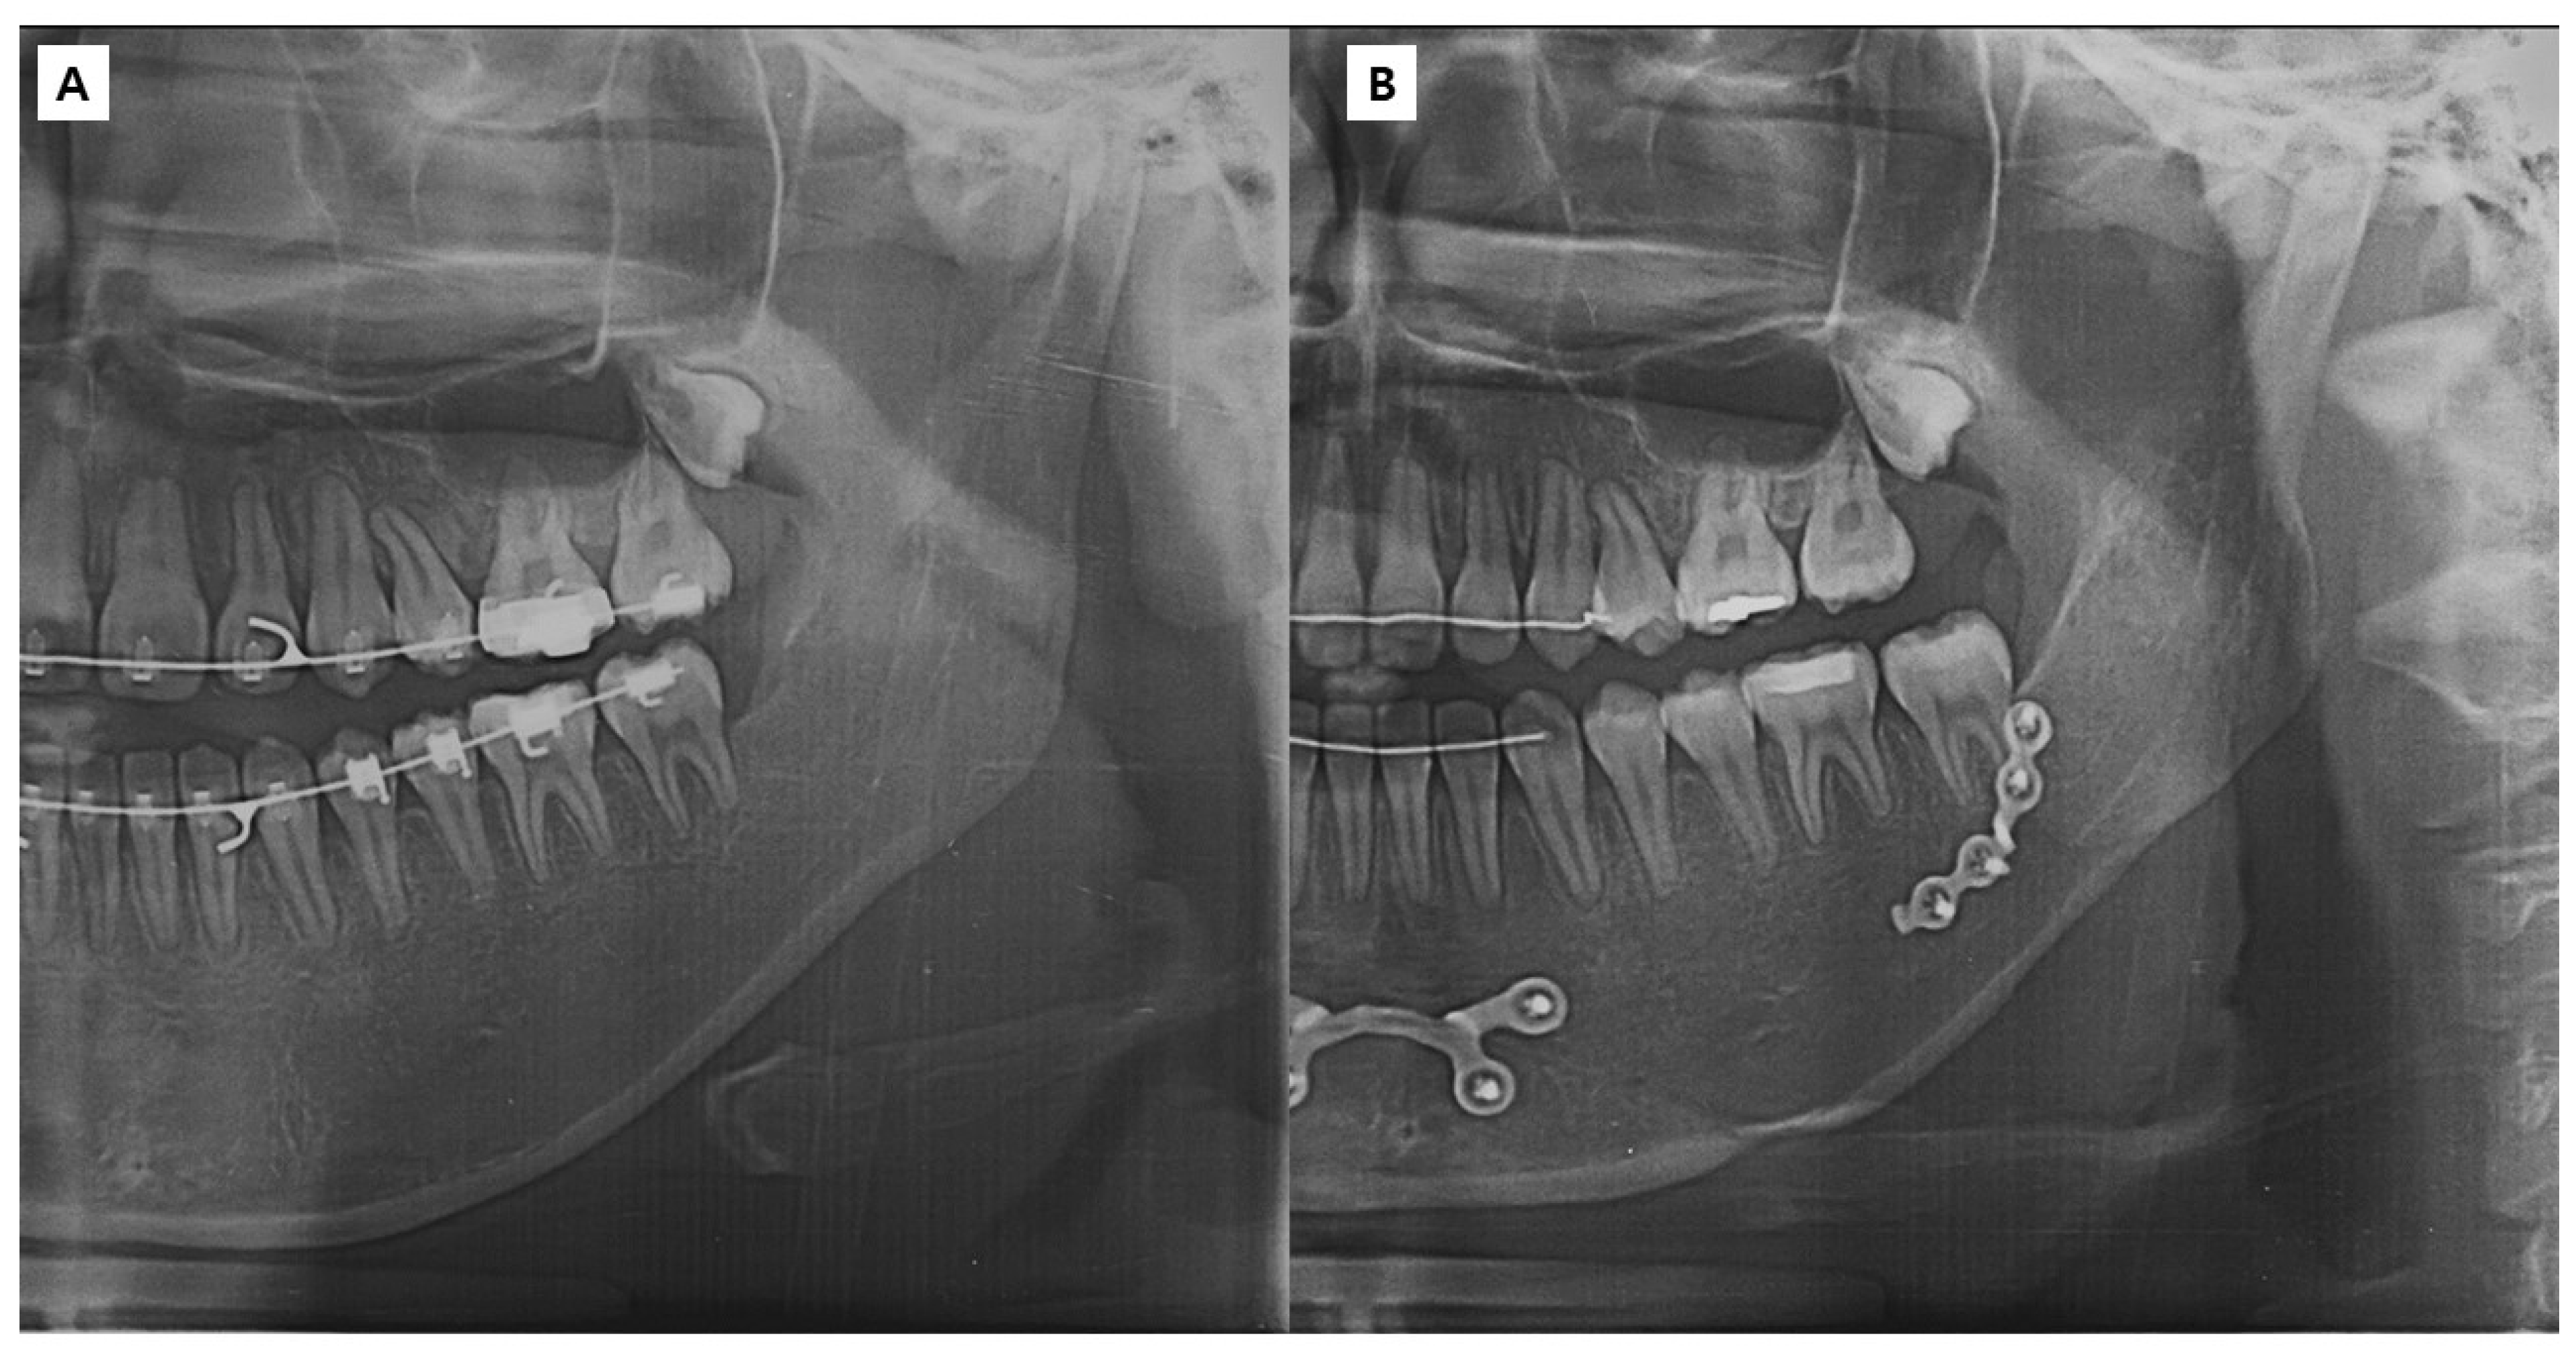

2.2.2. Surgery

2.3. Methods